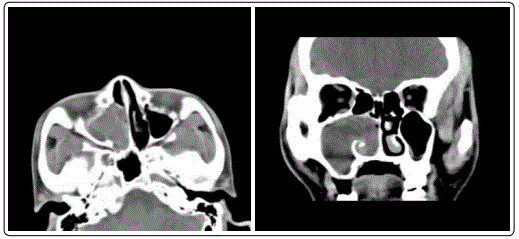

An 41 years old man with right nasal congestion for two months. Began to appear without apparent inducement right nasal obstruction patients nearly 2 months ago, was persistent, progressive increase, accompanied by headache and nasal, smell decline, no fever, nasal bleeding facial numbness and pain. Physical examination: nasal septum slightly left, right nasal see large amounts of red light with smooth surface and new biological purulent secretions. Before admission to hospital in nasal biopsy, pathological examination showed the right nasal fibroma. The relevant examination after admission, sinus CT (Figures 1 and 2) in soft tissue. The right maxillary sinus and the nasal cavity filled nasal soft tissue protrusion backward nostril, maxillary sinus enlargement, sinus wall bone damage. Under general anesthesia by nasal endoscopic resection of the right nasal cavity tumor and the anterior lacrimal fossa in right maxillary sinus tumor, Postoperative pathology (Figures 3 and 4) see yellow gray red tumor tissue, which arc shaped vascular tumor cells showed different degrees of atypia. The diagnosis was consider myxofibrosarcoma. Immunohistochemistry showed that the tumor cells of CK(±), Vim(+), BCL-2(+), S100(-), SMA(-), CD34(-), ALK(-), Des(-), CD99(-) Ki-67 about 30%(+). Postoperative given anti-inflammatory and hemostasis treatment, postoperative 4th day oncology follow-up treatment.